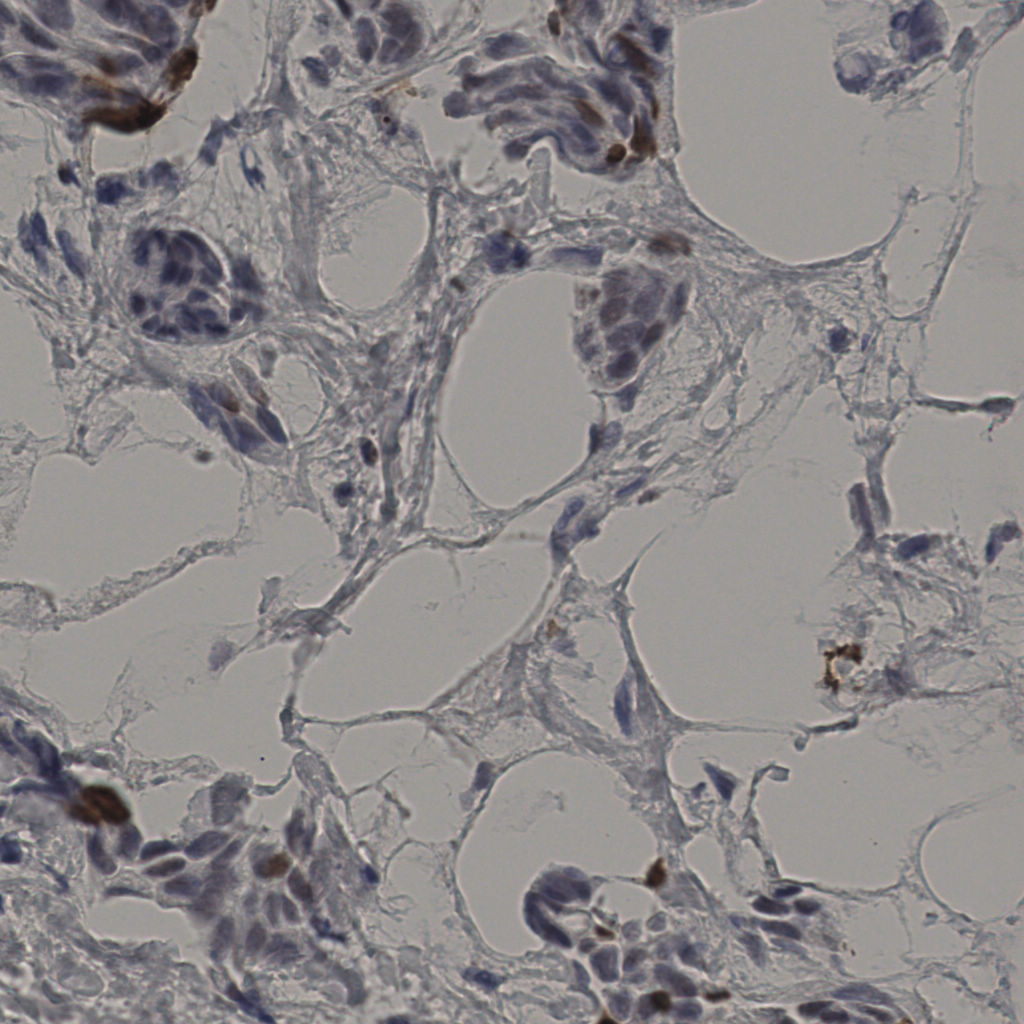

5.31%

Ki67 指数

阴 19502

阳 1093

缩略图

标记后

标记前